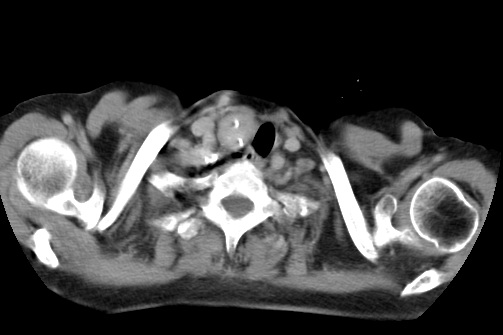

标题: CT23982:女67岁,胸部扫描时发现,甲状腺瘤? [打印本页]

标题: CT23982:女67岁,胸部扫描时发现,甲状腺瘤?

右侧甲状腺腺瘤!支持!不排除甲状腺癌可能!建议手术切除!

右侧甲状腺占位性病变,性质待定(甲状腺腺瘤?);建议:必要时行进一步检查。

右侧甲状腺占位性病变,性质待定(甲状腺腺瘤?);

右侧甲状腺占位性病变,性质待定(甲状腺腺瘤?);建议穿刺活检。

右侧甲状腺占位性病变,甲状腺腺瘤可能,建议穿刺活检。